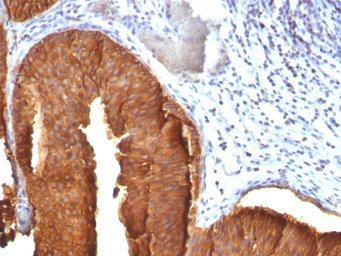

IHC-P analysis of human cervical carcinoma tissue using GTX34651 Cytokeratin 19 antibody [KRT19/800].